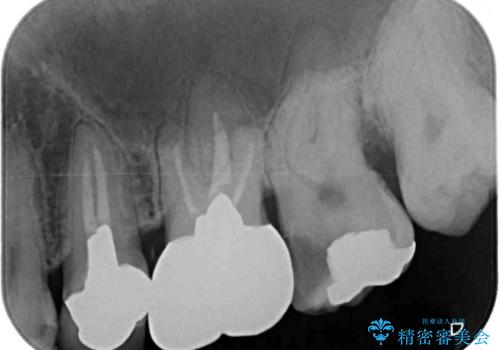

左上の奥歯は神経が失活しており、根管治療が必要な状態でした。

その他は銀歯のインレー(部分的な詰め物)が装着されており、それらはむし歯を除去した後にセラミックインレーにて修復治療を行い、左下と根管治療を行う左上の奥歯はオールセラミッククラウンにて補綴治療を行うこととしました。